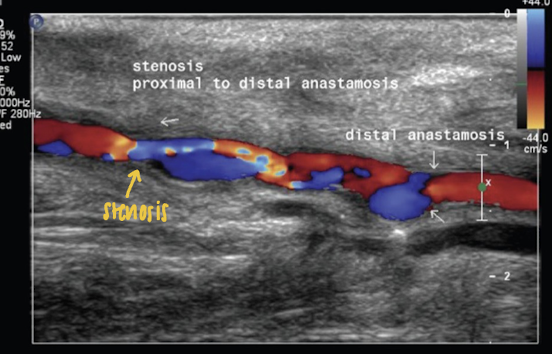

Color flow imaging of grafts

indicates mild changes in flow profiles

aliasing in stenosis

PSV ____ are considered abnormal

>180 cm/s

PSV with velocity ratio of 2

> 50% (PSV 180-300 cm/s)

PSV velocity ratio of 3.5

>75% stenosis (>300 cm/s)